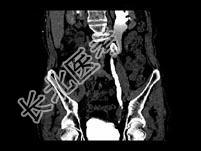

- 单项选择题男,76岁, 无痛性肉眼血尿3个月,CT检查如图所示, 下列说法错误的是 ( )

A、左侧肾盂扩张积水

B、左侧输尿管中上段扩张

C、左侧输尿管下段可见节段状不规则的软组织肿块影

D、考虑为左侧输尿管炎

E、考虑为左侧输尿管下段癌